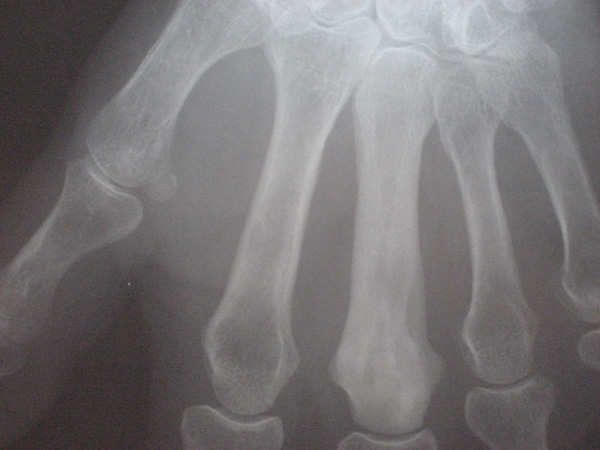

Cas clinique N°42

Imagerie

Cas a discuter

Dr Véra Lemaire Paris

Il s'agit d'une patiente née en 1930 qui consulte pour un gonflement des mains. Elle a un antécédent familial de PR. Il n'y a pas d'autre anomalie clinique que l'œdème des mains et des poignets.

L'hémogramme est normal, la vs à 35mms à la 1ère heure, la CRP est à 5. Il n'y a pas de facteurs rhumatoïdes, les anticorps anti-CCP sont à 19,4 pour une normale inférieure à 5.

Avec le diagnostic de RS3PE, elle est traitée par 10mg/j de prednisone pendant 15 jours, diminués à 7,5mg les 15 jours suivants.

Tout redevient normal :